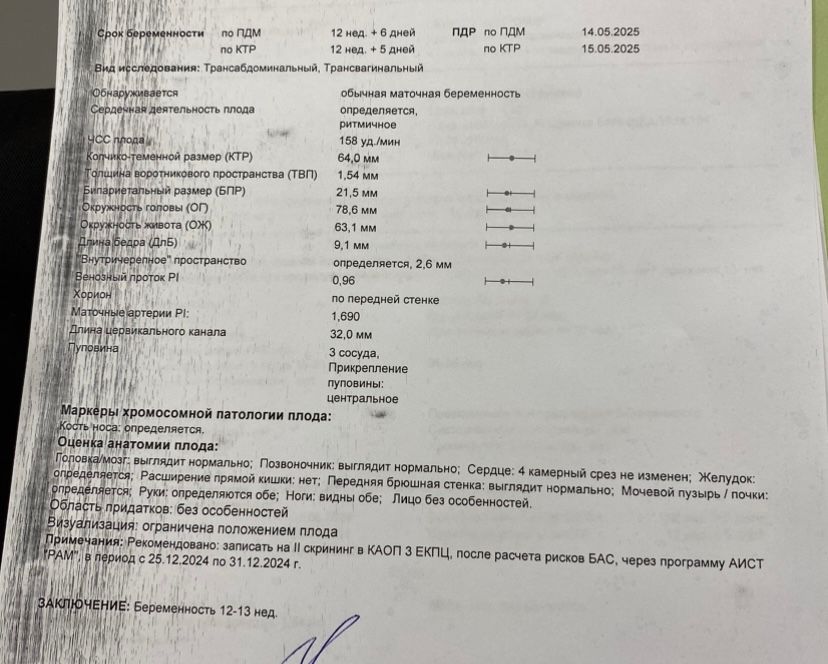

Поздравляю! А твп у вас в результате указан? Тоже сегодня проходила скрининг, но за твп данных нет в ЕМИАС, но в заключении написано норма все